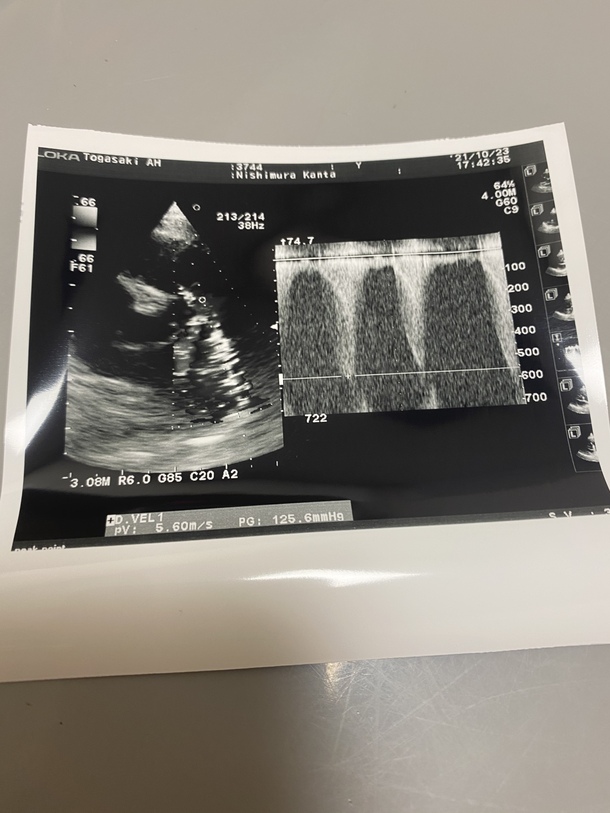

超音波検査の結果!!

本日通院day!

無事いつも通り帰ってこれました!

検査結果は

前回とほぼ同じ。とのことでした!

ですが心臓の筋肉量はどんどん増えていく一方で

どんどん手術が遅くなればなるほど

リスクはあがると説明されました。。